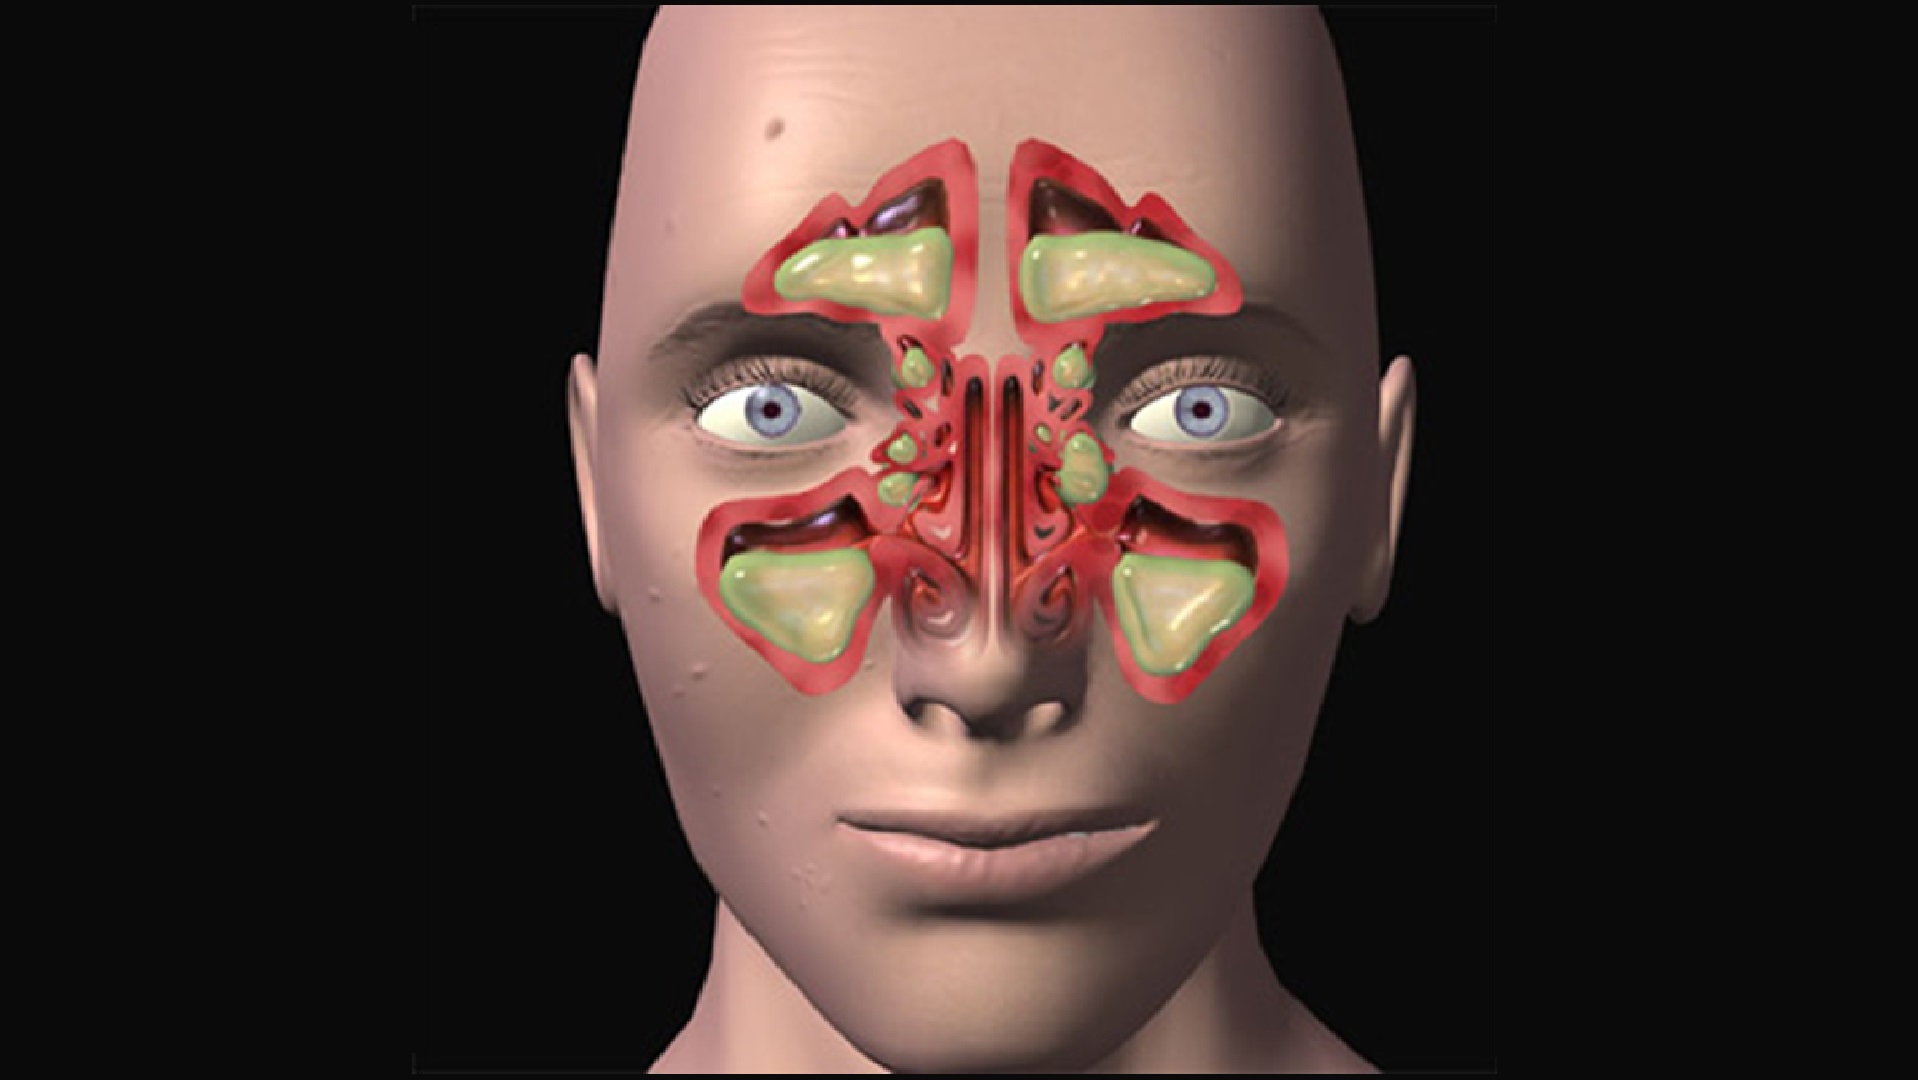

КТ-снимки хронического этмоидита: подробная визуализация